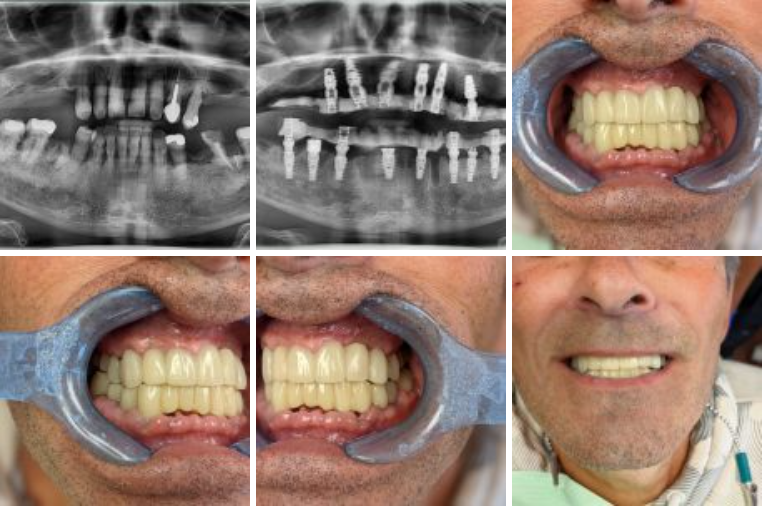

Пациент с не подлежащим восстановлению зубным рядом. Временные конструкции из ПMMA изготавливаются заранее.

Удалены зубы, немедленная установка имплантатов P7 и в день имплантации произведена нагрузка имплантатов временными конструкциями из ПММА, винтовая фиксация на мультиюнитах S16S и S17S. Тотальная реабилитация за два визита.

В исполнении: Доктор Джастин Брал

Иерихонский стоматологический центр